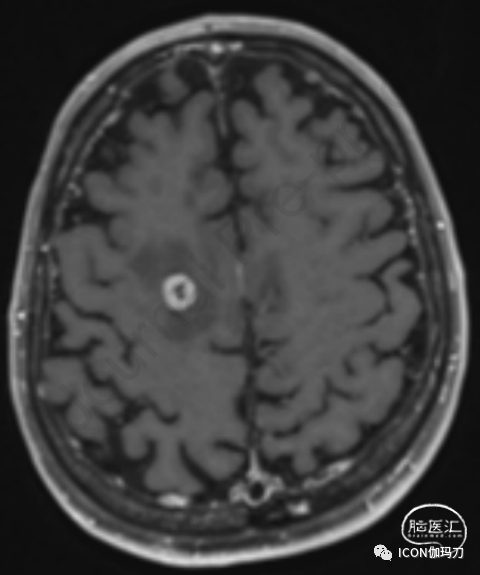

使用ICI与发生RN的风险增加相关。图1展示了1例患单个额顶叶脑转移的患者的轴位MRI图像,该患者同步接受了SRS和ICI,之后发生了影像学定义的RN。ICI已被证明可增加组织内CD8+T细胞的浓度,这可能与历史上被归类为RN的MRI表现相关,但可能代表TRIC,因为这两种治疗之间的协同作用增强了抗肿瘤免疫。因此,TRIC在历史上被归类为RN,其存在可能作为ICI和SRS反应增强的影像学标志物。

图1。同步接受立体定向放射外科和免疫检查点抑制剂治疗的患者的轴位MRI切片。MRI描述了一个影像学定义的放射性坏死病例,该病例经药物治疗后无并发症